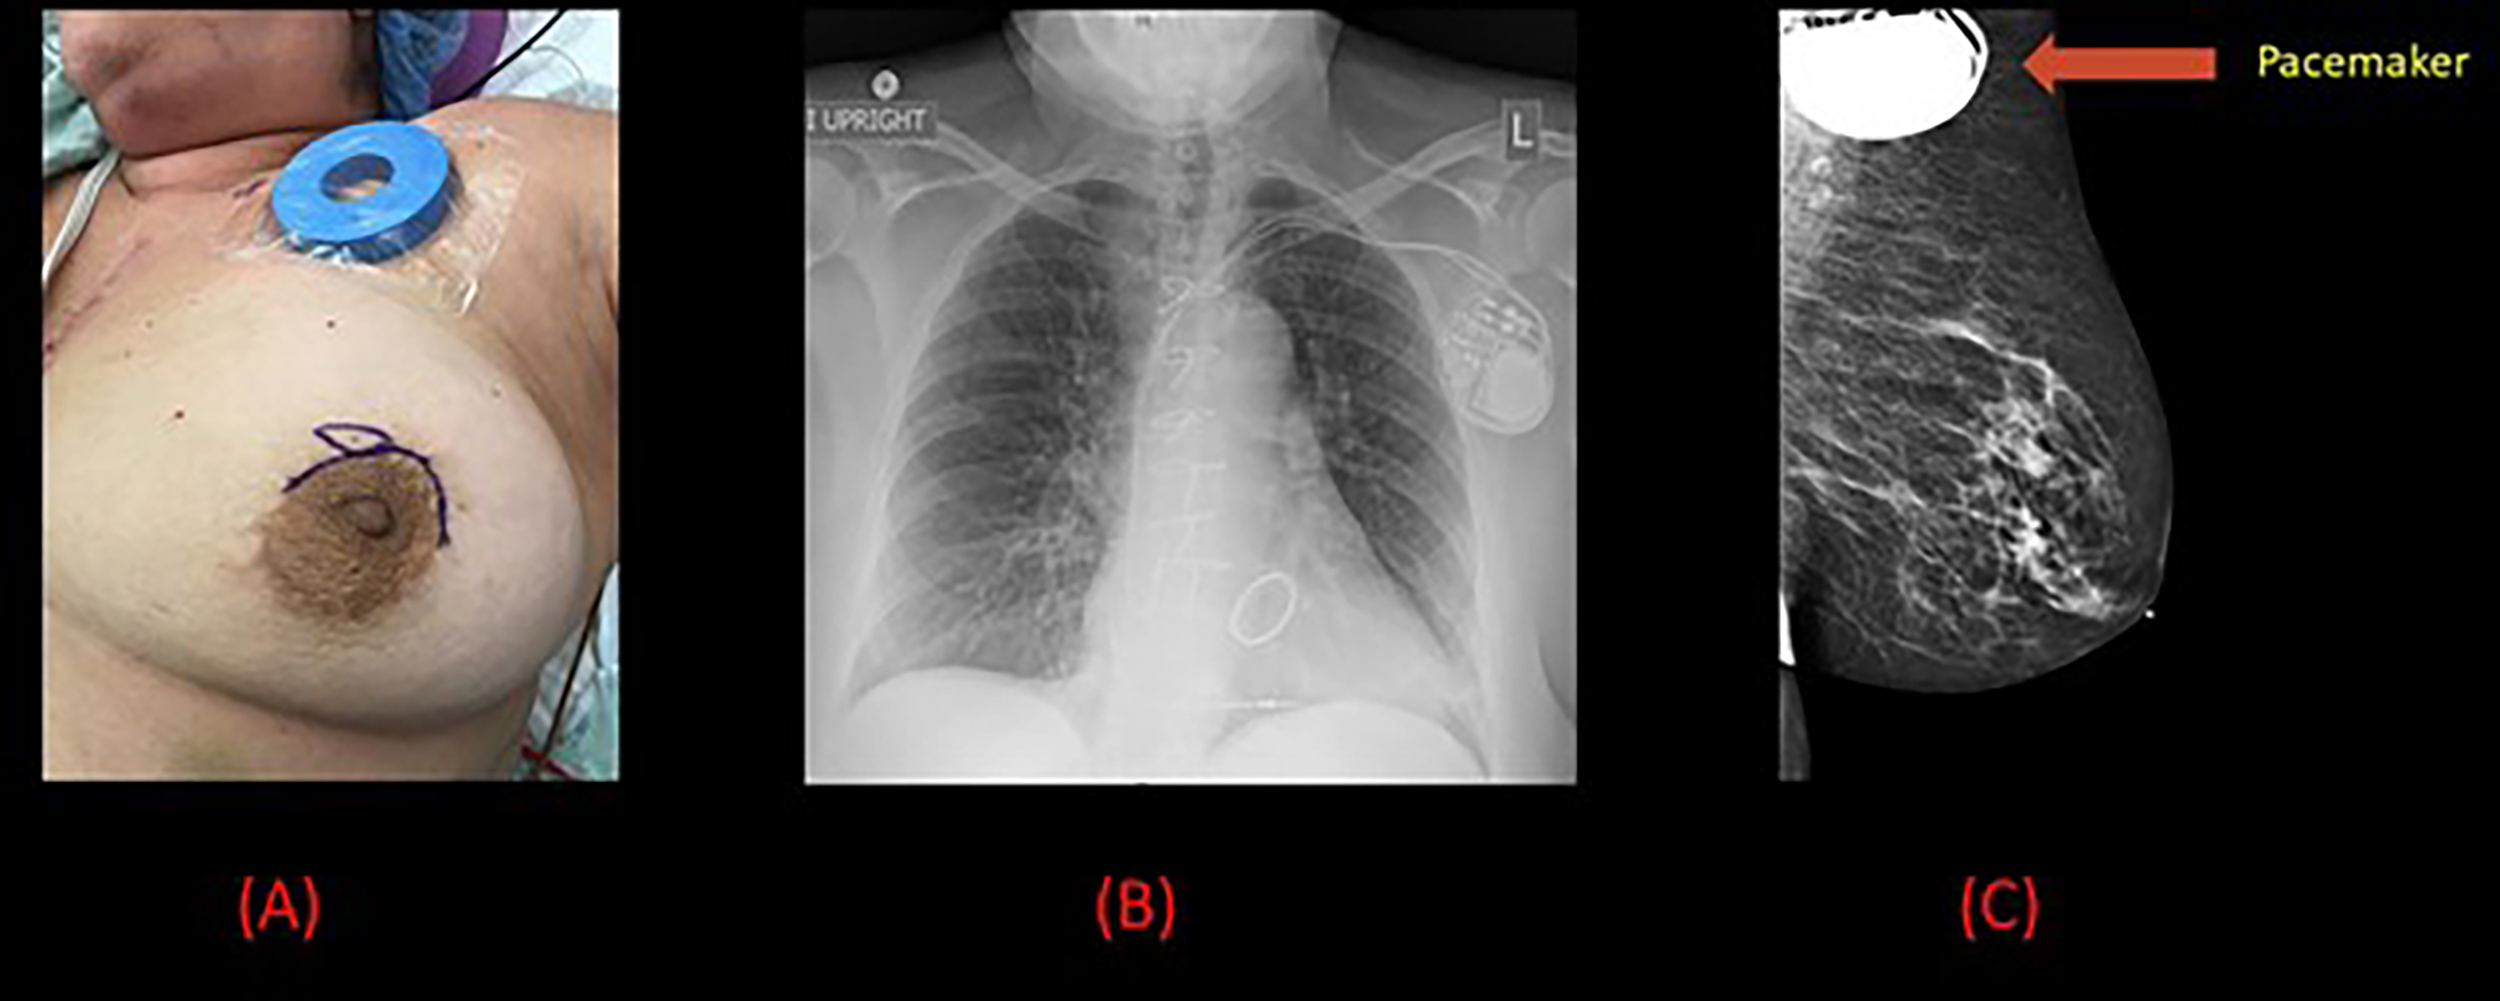

Figure 3 Pre-operative and radiological images for patient 2. (A) Pre-operative image of the left breast with a magnet placed on the pacemaker and surgical marking indicating the tumor site. (B) Chest x-ray demonstrating left sided pacemaker with leads projecting over the right atrium and right ventricle. (C) Mammogram demonstrating a 7 mm spiculated mass in the left breast along with the pacemaker.

A 64-year-old female with a history of surgically managed right invasive lobular carcinoma with lumpectomy, sentinel lymph node biopsy, and whole breast radiation 6 years back presented with an incidental finding of a 7 mm spiculated mass in the anterior to middle depth at 12:00 axis of the left breast on a routine follow-up mammogram (Figure 3). An ultrasound guided core biopsy revealed clinical stage I T1 (7 mm) N0 grade 2, ER +, PR + Her2 – invasive ductal carcinoma and a focal ductal carcinoma in situ (DCIS), nuclear grade 2, cribriform type. The patient also had a history of atrial fibrillation, hepatitis C, asthma, chronic obstructive pulmonary disease (COPD), mitral stenosis, pulmonary hypertension, mitral valve replacement, cerebrovascular accident, and dual-lead pacemaker (DDD mode, model Medtronic type AZURE XT DR MRI) implanted for Mobitz type II heart block. The pacemaker was programed to a lower rate of 60 bpm and a maximum of 130 bpm. Anatomically, the pacemaker was placed in a subcutaneous pocket in the upper pole of the left breast, 10 cm away from the primary tumor.

Patient underwent wide local excision followed by TARGIT-IORT during surgery delivered with the help of an Intrabeam 600. The distance from the applicator to the skin was then measured using ultrasound, with the closest bridge being inferior at 20 mm. IORT was delivered with using a 35-mm diameter spherical applicator, which delivered 20 Gy to the surface of the surgical margin in direct contact with the applicator for a duration of 16 minutes. During treatment, an OSLD was placed on the skin surface beneath the radiation shield, close to the pacemaker site, for in vivo dosimetry. The measured absorbed dose from the Intrabeam IORT system radiation on the skin surface near the pacemaker site was estimated to be 0.185 Gy.

Both the surgery and the TARGIT procedures were successful. The procedures were well tolerated by the patient, and there was no malfunction of the pacemaker device during surgery or IORT. The patient made an uneventful recovery and was discharged the same day. Histology confirmed the presence of a 12 mm grade 2 invasive micropapillary carcinoma excised with clear margins. The tumor tested positive for ER/PR but negative for Her-2.